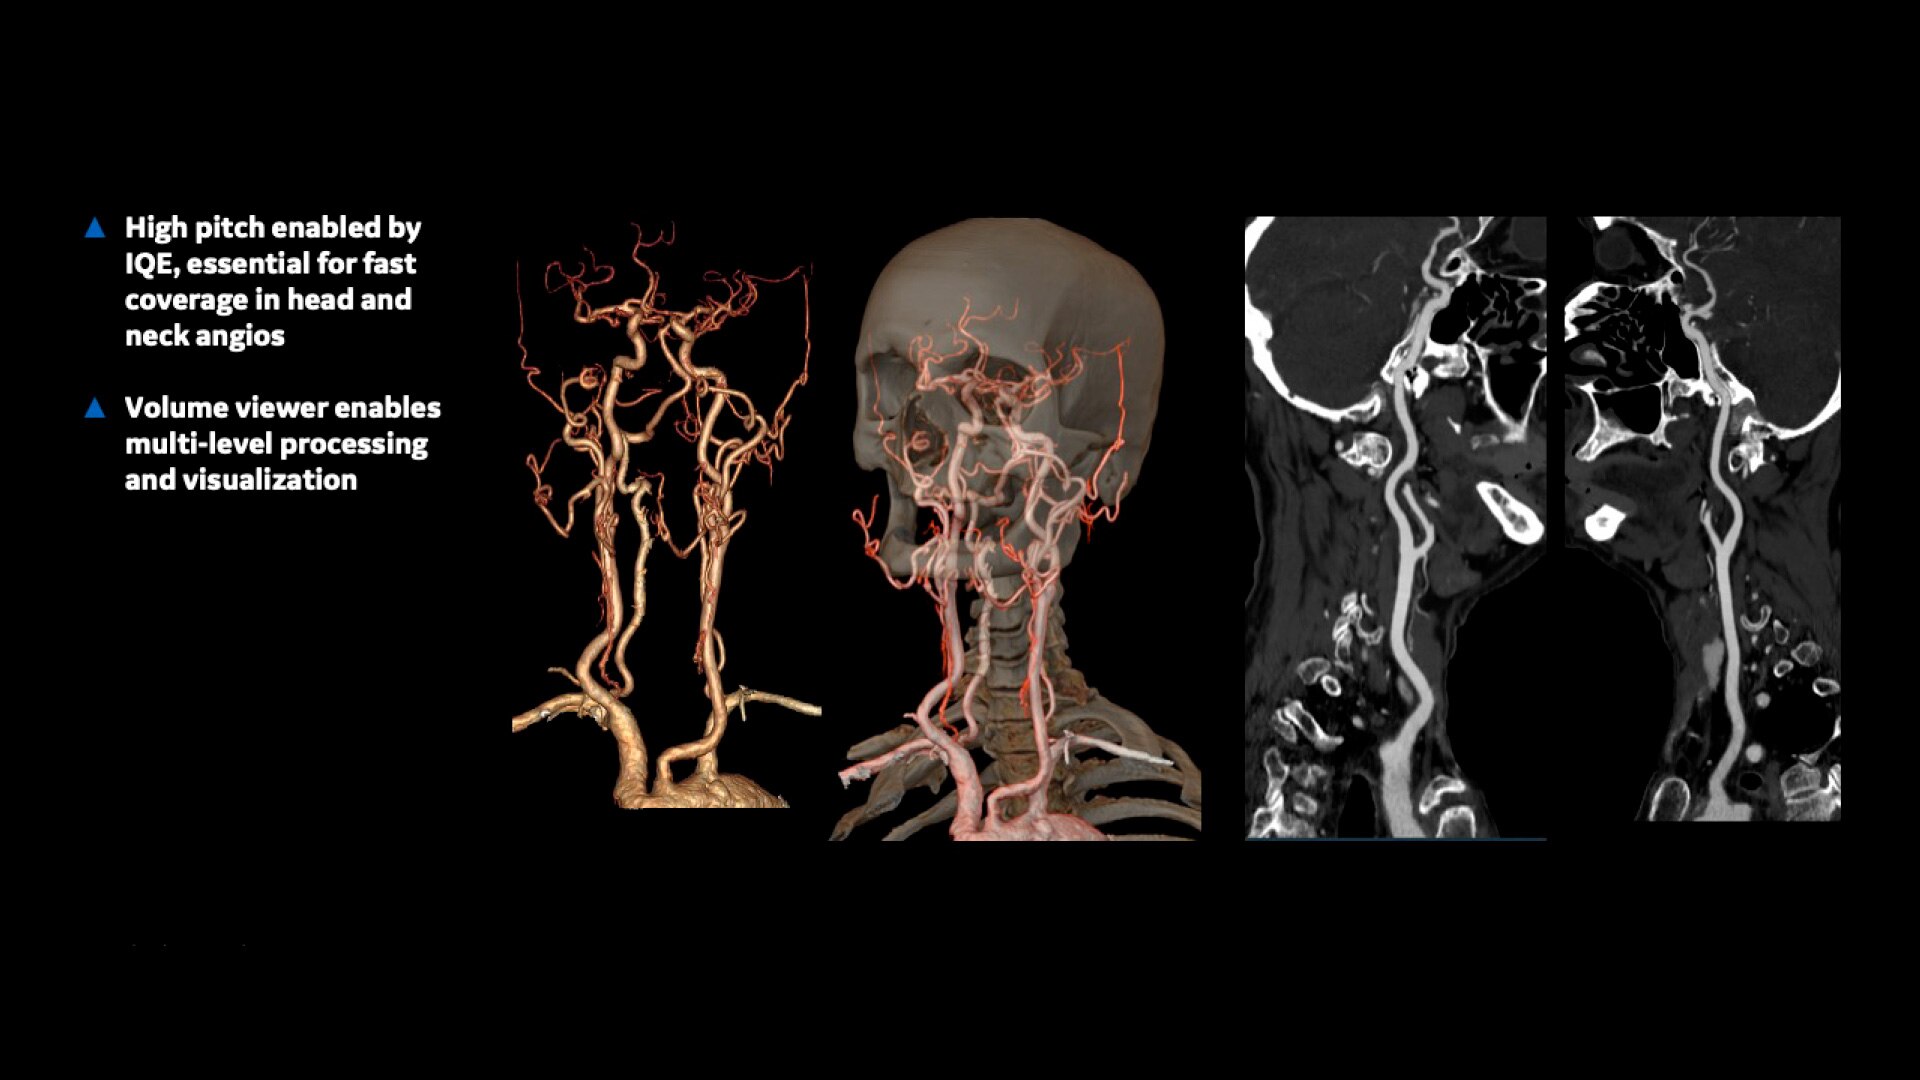

Volume Viewer – Provides information about the spatial relationships using volume rendering, multi-planar reformat, and MIP/min-MIP.

Vascular Imaging and Processing – Enhances analysis of vascular features by automatically determining vessel centerline and tracking multiple vessels.